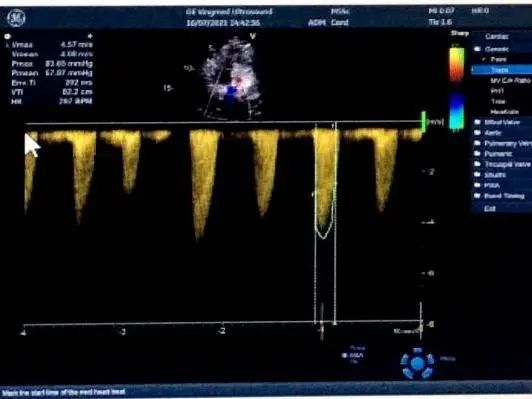

术前测量,患者主动脉峰值流速452cm/s,平均跨瓣压差36mmHg,术中通过患者左侧锁骨下动脉建立辅入路,造影示主动脉根部明显钙化,左室内中量反流影像。

造影,超声示微量瓣周漏,术后平均跨瓣压差5mmHg,主动脉血流峰值流速1.7m/s,患者血流动力学指标显著改善。